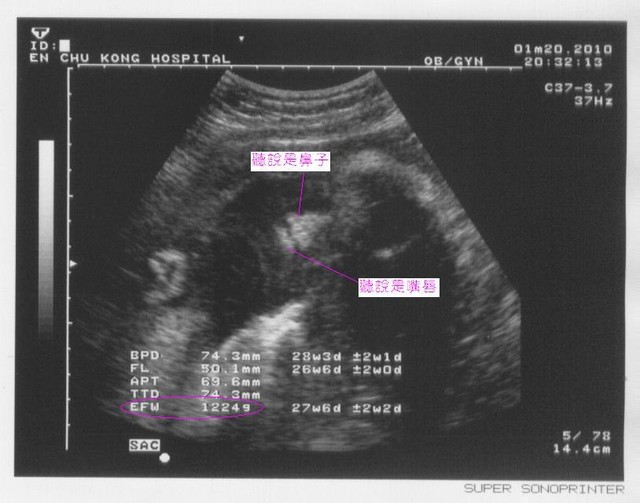

|

2010.01.18高層次超音波 |

2010.01.20例行產檢 |

週數 |

28週又3天 |

28週又5天 |

頭骨橫徑 |

7公分 |

7.43公分 |

大腿骨橫徑 |

5.16公分 |

5.01公分 |

預估體重 |

1178公克 |

1124公克 |